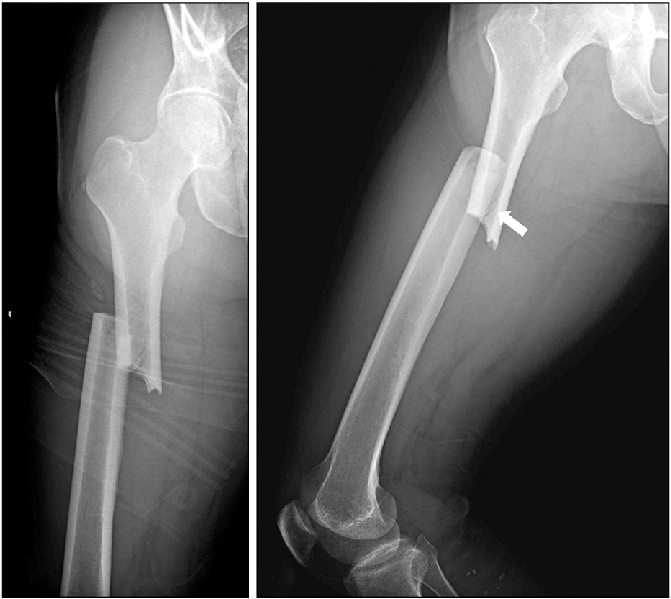

Pathological Fracture - आजारामुळे हाडे कमजोर होऊन तुटणे.